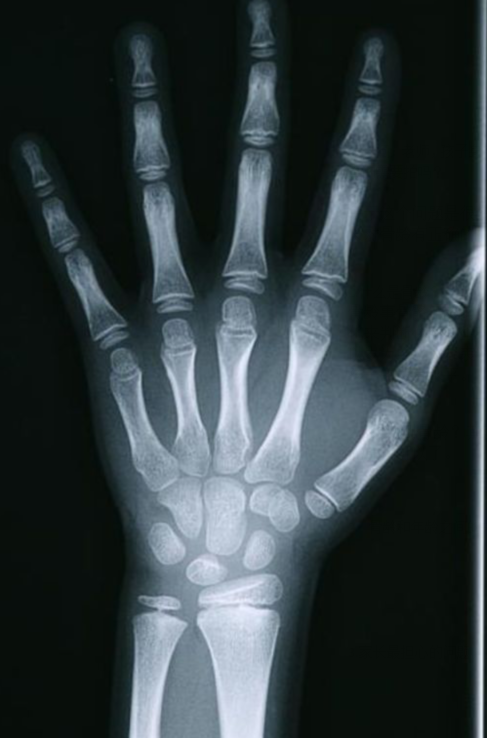

骨骺线是骨骺与干骺端之间的软骨,它在x光片上表现为一条较宽的透光带